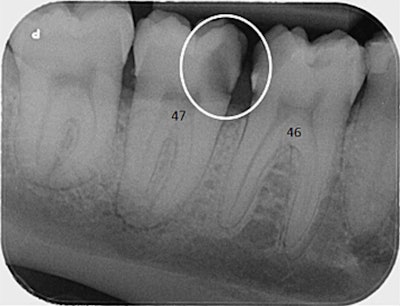

(d) Initial periapical radiograph of tooth 47 shows a cavity on the mesial side (white circle). Images and captions courtesy of Geusens et al. Licensed under CC BY-NC-ND 4.0.

About four months after the treatment, the man went to hospital after his dentist referred him. A periapical x-ray revealed an infection and periapical osteolysis, and a cone-beam computed tomography (CBCT) scan revealed a complete sequestration of the interdental septum between teeth #46 and #47, as well as periapical osteolysis extending to the mandibular canal, the authors wrote.